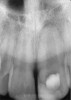

Clinical procedure: Regeneration of the endodontic pulp space is indicated for cases with very thin dentinal walls and an open apex that is more than 1 mm in diameter radiographically (Figure 4). Disinfection of the root canal system is performed using sodium hypochlorite irrigation followed by a triple antibiotic paste dressing that is left in place for 1 week. At the second visit, ethylenediaminetetraacetic acid (EDTA) is used to condition the dentin walls, which results in the release of growth factors, and bleeding is stimulated in the periapical tissues (where stem cells are located), with the aim of filling the pulp space with a stable blood clot, which would serve as the scaffold. MTA is then placed at the canal orifice in contact with the clot to protect it from coronal microleakage (Figure 5 and Figure 6). In time, the clot should be replaced with a reparative tissue of variable composition, and the root walls should continue to thicken due to the deposition of a dentin-like material on the pre-existing root dentin27,28 (Figure 7 and Figure 8).

Fig 4. Preoperative radiograph showing aggressive external root resorption and thin dentinal walls.

Figure 4